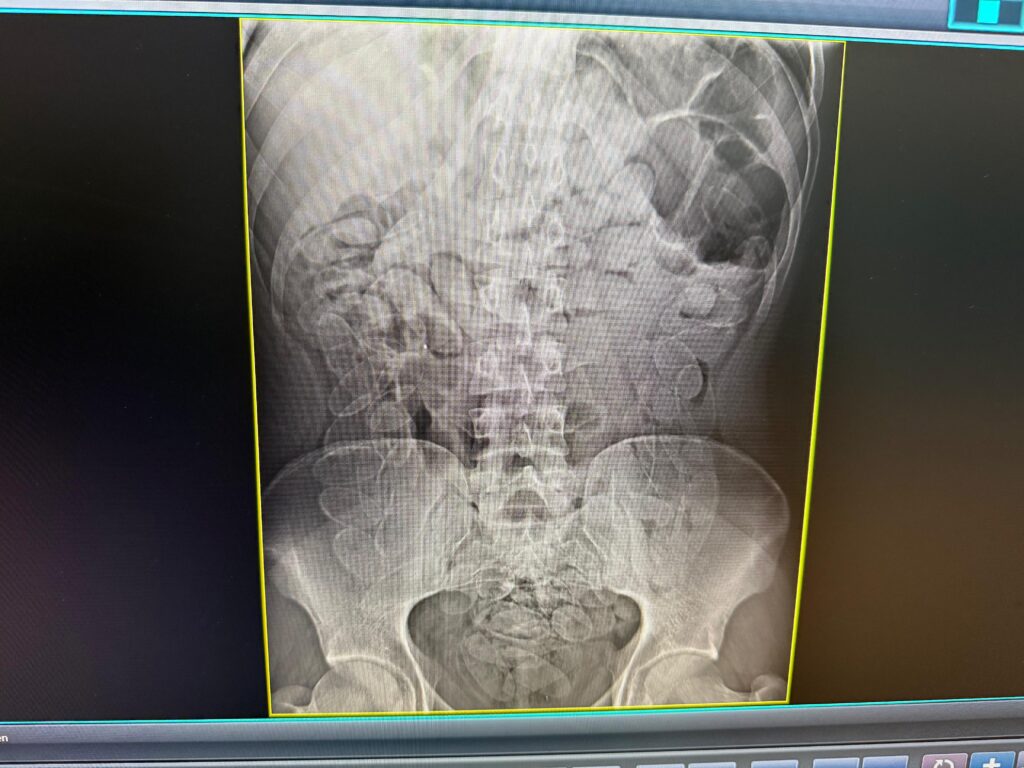

O outro passageiro, um homem de 24 anos, demonstrou excessivo nervosismo e indícios que havia ingerido cápsulas de drogas. Ambos de nacionalidade boliviana foram encaminhados para a Santa Casa de Corumbá. Foi constatado que o passageiro havia engolido 90 cápsulas e seguiu no hospital para que a substância fosse expelida com segurança. Eles receberiam R$ 2,5 mil e, após os devidos procedimentos médicos e administrativos, foram encaminhados para a Polícia Federal.